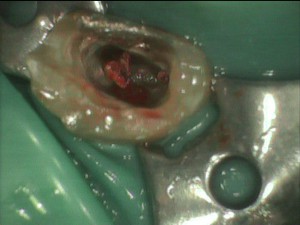

上は血の池になっていた初診時の写真です。

これは抜歯したほうが・・・と思いました。

しかし、保存を強く望まれたので、MTAでパーフォレーションリペアを試みます。